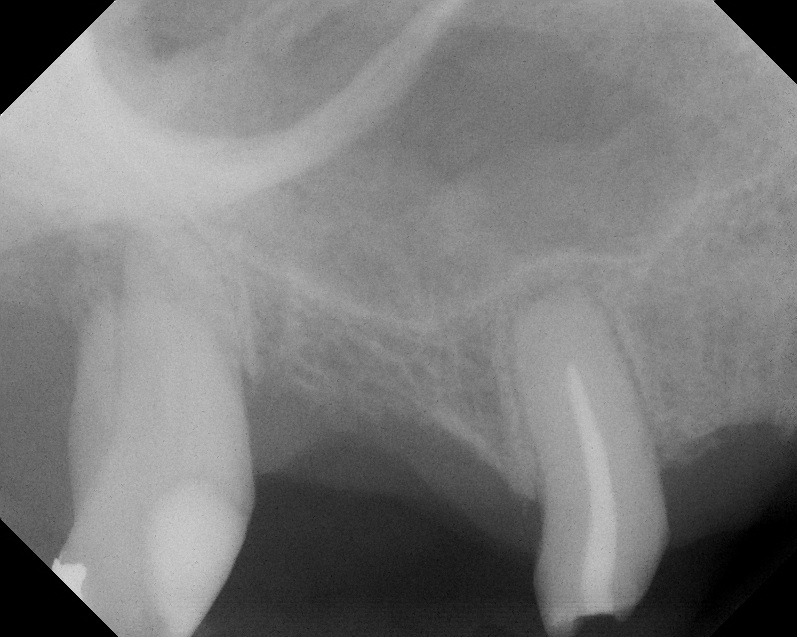

Case 2. Preoperative ridge in the No. 14 position. The height of native bone is about 4 mm to 5 mm.

Fig. 17

A 16-month postoperative radiograph showing stable bone. The patient refused treatment

of tooth No. 15, which has endodontic involvement.

Fig. 18

A 74-year-old male patient presented with about 4 mm to 5 mm of native bone in the No. 4 position (Figure 17). A composite graft, as described in Case 1, was used, as was the same implant type, but the implant was 11.5 mm in length with a taper of 5 mm to 4.2 mm. The approximately 16-month post-healed floor of the sinus was raised about 7 mm to 8 mm (Figure 18). The CBCT scan taken at 16 months postoperatively showed no change in appearance from the area of the old floor of the sinus to the new bone formed (Figure 19). Although it was endodontically involved, tooth No. 15 was not extracted, against professional advice. As can be seen in Figure 18, the No. 14 implant is acting as a bridge abutment.